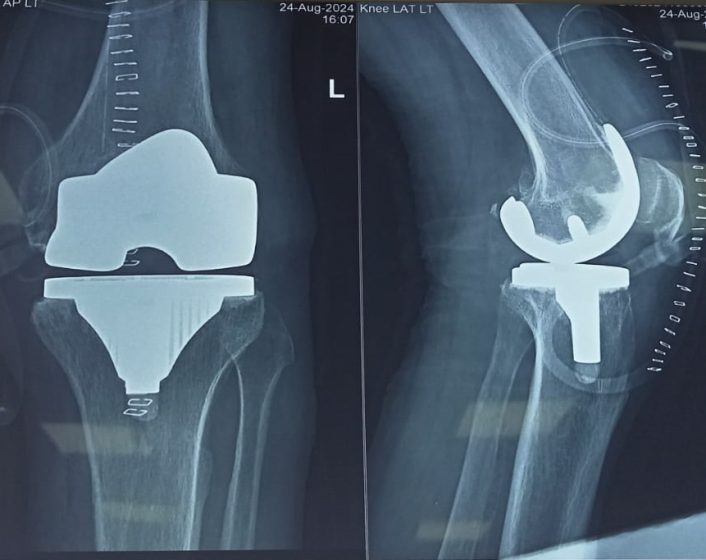

Knee replacement

Genuine varum deformity in knee arthritis